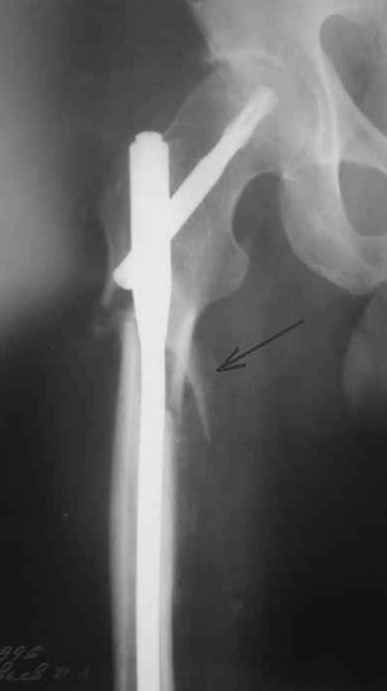

На операции я оставил осколок в области приводящих мышц бедра (ни пальпаторно, ни спицей сдвинуть не смог, "заклинило" насмерть). Фото спустя 2 месяца после операции (PFN).

Только сейчас пациент стал более или менее активным. Сразу после операции жалобы на сильные боли при отведении и приведении бедра в области отломка. Сейчас отломок пальпируется и пациент испытывает дискомфорт, хотя амплитуда движений объективно прогрессирует.

Теперь думаю, надо все-таки было через минидоступ или резецировать, либо репонировать. Обычно при таких операциях уже на 2-й день пациенты на костыли и по отделению, а у этого задержка длительная получилась. Только спустя 2 недели кое-как на костыли взобрался. Ни отека, никакой неврологии, только эти боли в области осколка.